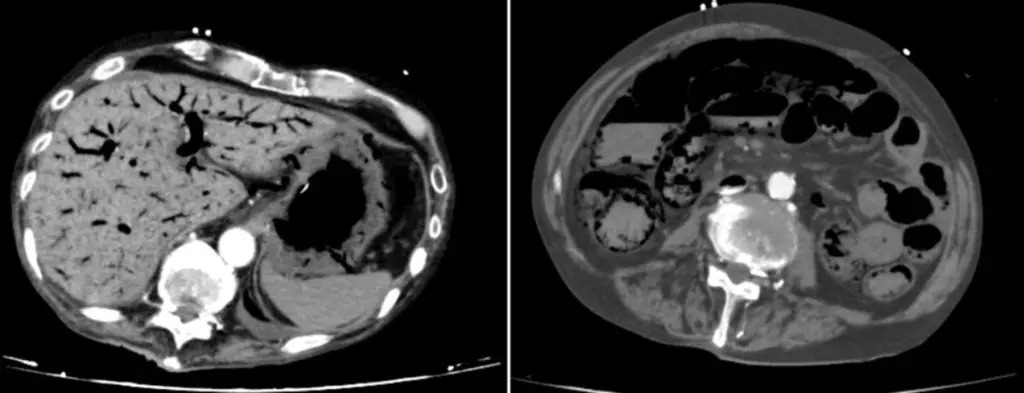

وعلى الرغم من تحسن حالته المبدئية، بدأت الأمور في التدهور بعد مرور حوالي 25 يومًا من خروجه من وحدة العناية المركزة، إذ بدأ يشعر بألم مستمر في المعدة، وساءت حالته بسرعة وأصيب بفشل في العديد من أعضاء الجسم، وتوفي بعد شهرين تقريبًا من دخوله المستشفى، وكان الرجل يعاني من بكتيريا الدم، بسبب تناول البروبيوتيك، بالإضافة إلى نقص تروية المساريقا غير الانسدادي، وهو حالة تتميز بانخفاض تدفق الدم المعوي.